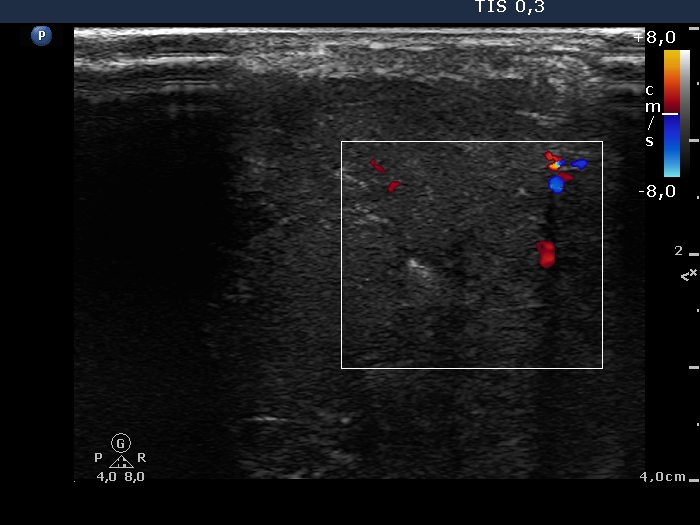

Thyroid cancers - case 199 (ultrasonographic picture 5)

Left lobe, longitudinal scan, color Doppler mode. The vascularization is decreased.